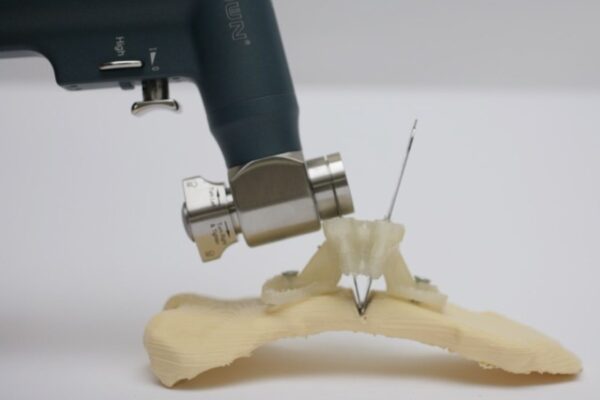

Ameliyat sırasında, sternum (iman tahtası) ile kaburgalar arasındaki düzensiz kıkırdak segmentleri çıkarılır,

ardından sternum doğru anatomik konumuna getirilir ve gerekirse destekleyici materyallerle stabilize edilir.